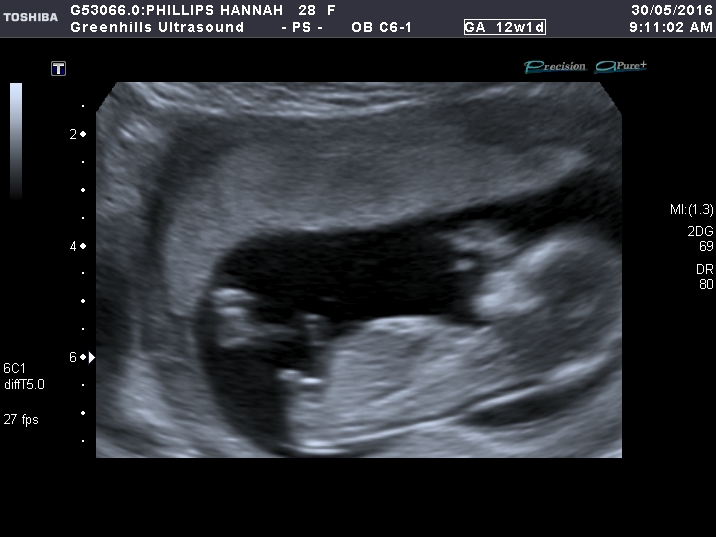

Top pic is at 12 weeks